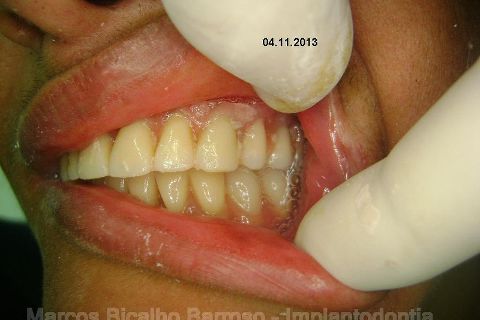

Atualização do caso clínico que já postei, "REABILITAÇÃO EM MAXILA ATRÓFICA COM IMPLANTES", um caso que inclui expansão do rebordo estreito com cinzel e martelo, expansores rosqueáveis, enxerto e instalação dos implantes distais inclinados tangenciando seio maxilar. Inclui esvaziamento do forame nasopalatino e preenchimento com biomaterial para instalação de dois implantes próximos dele. Cirurgia realizada em única sessão, com instalação dos 6 implantes. Para os colegas que não conheceram e/ou esqueceram da apresentação, este é o resumo do caso na fase cirúrgica.http://www.youtube.com/watch?v=BtvexFexRPA&hd=1

FASE PROTÉTICA DA REABILITAÇÃO EM MAXILA ATRÓFICA...incluindo a reabertura, instalação dos minipilares e PTR provisória reembasada sobre os cilindros de proteção.